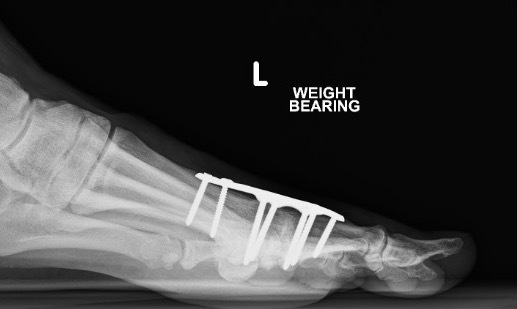

Arthrodesis

Indication

- advanced OA

- young, active patient

Screw fixation

Plate fixation

Screw + plate fixation

Approach

- dorsal approach

- medial approach

Position

- 10 - 15° valgus

- 10- 15° dorsiflexion relative to plantar surface / 20 - 25° relative to metatarsal shaft

Fixation

- screws / plate / screws + plate

Results

- 4 year follow up of 60 1st MTPJ fusion

- screw + plate

- 93% fusion

- remainder painless pseudoarthrosis

- 72% very satisfied, 18% satisfied